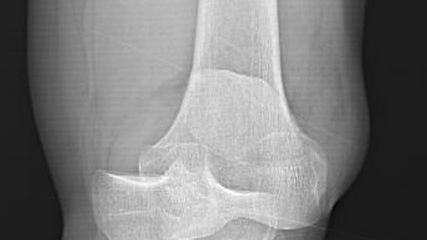

Eine Evidenzlücke hat PD Dr. med. Peter Behrendt, Oberarzt in der Klinik für Orthopädie und Unfallchirurgie Kiel im Universitätsklinikum Schleswig-Holstein, geschlossen: In einer Studie1 zeigte er, dass die autologe matrixinduzierte Chondrogenese (AMIC) bessere patientenrelevante Ergebnisse liefert als die «Minced cartilage»-Technik (MCI) – womöglich deshalb, weil sich die Stammzellen bei der AMIC besser in Ruhe differenzieren und Knorpel bilden können. Die Reparatur von Knorpelschäden im Knie ist trotz moderner Therapieverfahren eine Herausforderung.Denn wenn der Knorpel einmal geschädigt ist, regeneriert er sich nicht wieder.2 Um den Knorpel erfolgreich therapieren zu können, ist eine ausführliche Diagnostik essenziell. Hierzu gehören Standardröntgen, Magnetresonanztomografie, in besonderen Fällen eine Computertomografie zur Beurteilung von spezielleren Aspekten des subchondralen Knochens, eine Aufnahme des gesamten Beines, um die Beinachse zu beurteilen, und allenfalls gehaltene Aufnahmen zur Einschätzung der Gelenkstabilität. Bei der Diagnostik sollte geklärt werden, ob der Knorpelschaden die Ursache für die Beschwerden des Patienten/der Patientin ist, welche Ursache der Knorpelschaden selbst hat und ob dieser im Rahmen der Therapie gleich mitbehandelt werden kann.

Eine gute Orientierung für den Praxisalltag, in welcher Situation welche Technik infrage kommt, bietet die aktuelle Empfehlung zur Behandlung von Knorpelschäden am Kniegelenk der Arbeitsgemeinschaft Klinische Geweberegeneration der Deutschen Gesellschaft für Orthopädie und Unfallchirurgie.4,5 Nach sorgfältiger Diagnostik, Analyse der Eignung des Patienten/der Patientin für den Eingriff und Festlegung allfälliger Begleiteingriffe wird das geeignetste Therapieverfahren anhand der Defektgrösse ausgewählt (Abb. 1). Die autologe Chondrozytentransplantation (ACT) erfolgt zweizeitig, die übrigen Verfahren wie die MCI, die AMIC, die osteochondrale Transplantation (OCT) oder die Allograft-Transplantation einzeitig. Bisher gibt es wenige randomisierte klinische Vergleichsstudien zu den einzelnen Verfahren.